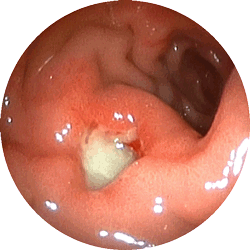

十二指腸潰瘍2

十二指腸潰瘍

嘔気(吐き気)と鈍い痛みで

来院

内服薬1ヶ月で治癒